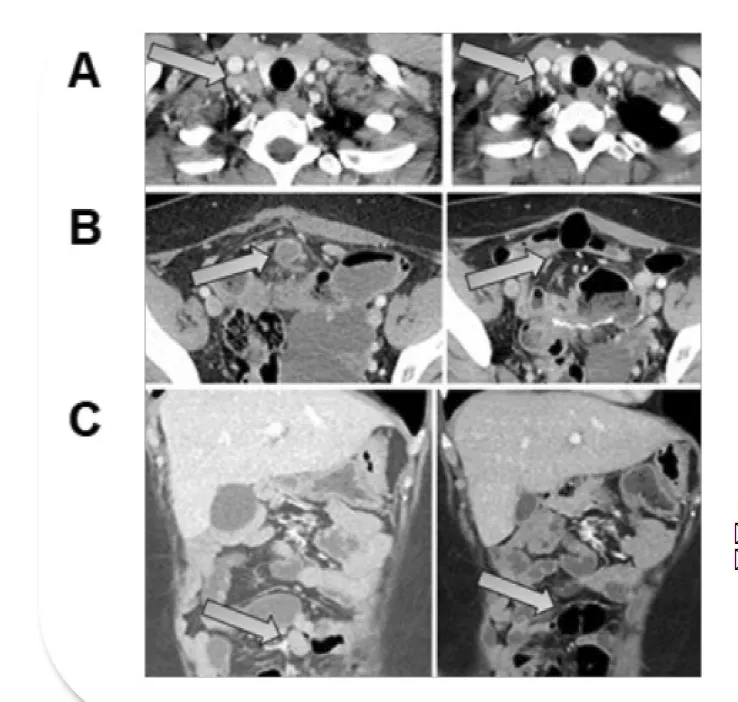

除ASCO公布的最新数据外,GT201联合PD-1抑制剂治疗晚期头颈部鳞癌的单臂临床研究,也在上海九院取得亮眼成果——首例口腔癌受试者已实现完全缓解。该受试者为61岁男性,2016年因喉癌接受手术及辅助放化疗后治愈,2023年9月确诊口底癌(属头颈部鳞癌,伴下颌骨侵袭及颈部多发淋巴转移)。因手术可能导致严重语言、吞咽功能障碍及外形损伤,患者放弃手术,且多轮化疗、靶向治疗后肿瘤仍快速进展,最终入组接受GT201治疗(配合桥接治疗及后续维持治疗)。

治疗结果显示:TIL输注后仅3周,患者病灶显著缩小达到部分缓解(PR);治疗9周随访时,影像学评估显示所有病灶完全消失,成功实现完全缓解(CR)(详见下图)。

▲图源“上海九院官网”,版权归原作者所有,如无意中侵犯了知识产权,请联系我们删除